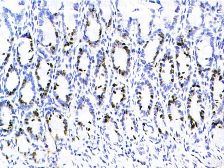

SABC法染色,DAB显色

大鼠小肠腺细胞核呈棕色为BrdU免疫反应阳性